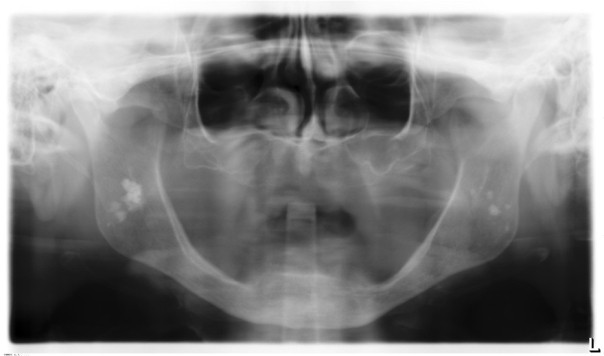

3 / 25

3. (Select ONE OR MORE correct answers)

The radiograph shows evidence of